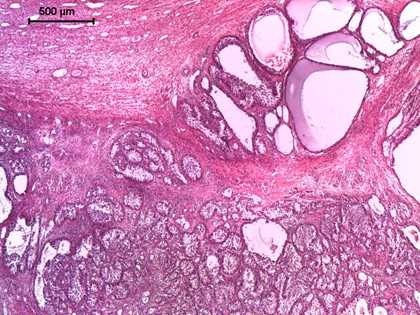

Cel: diagnostyka ziarniszczaka (GCT) u klaczy oraz wnętrostwa/pozostałości tkanki jąder u samców, kontrola po kastracji (

brak rui lub nieregularne cykle (ciąża i cykle płciowe nie wykluczają występowania GCT)

zmiany zachowania – od nimfomanii po zachowania ogierze, ale często bez zmian

zwykle jeden jajnik znacznie powiększony, drugi nieaktywny (mieć na uwadze, że guzy mogą być obustronne)

wyższe prawdopodobieństwo u klaczy w wieku >10 lat, jednak możliwy w każdym wieku